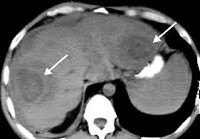

КТ ОБП. Подкожное повреждение правой доли печени с газовыми включениями (абсцесс печени).